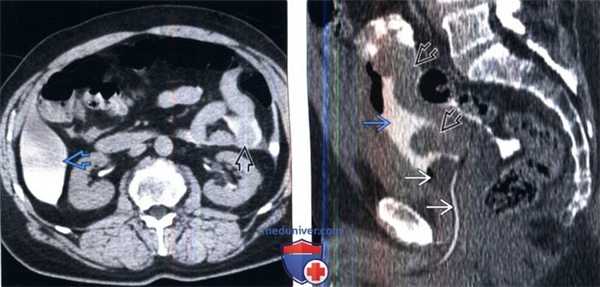

(Слева) КТ с контрастированием после цистографии, аксиальный срез: экстравазат контрастируемой мочи, окружающий матку, яичники и петли тонкого кишечника. Эти признаки характерны для внутрибрюшинного разрыва мочевого пузыря.

(Справа) КТ с контрастированием после цистографии, аксиальный срез: экстравазат контрастируемой мочи в околопузырных пространствах, вследствие внебрюшинного разрыва мочевого пузыря. Визуализируются несколько пузырьков газа глубоко в прямых мышцах живота, вследствие травмы мягких тканей и перелома таза.